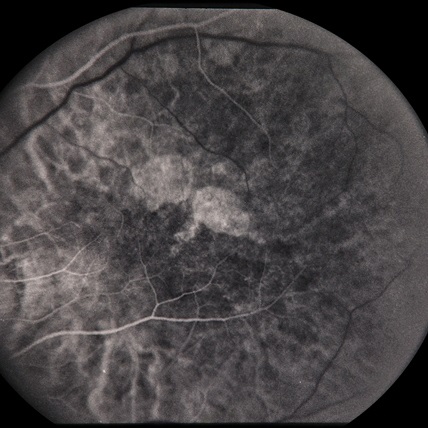

4.4 DCGANs and WGANs

In this section, DCGANs and WGANs are trained with thousands of CFP and FA images that have symptoms of drusen and GA separately; both of the models require four to six hours to train. Generated images have been diagnosed by ophthalmologists for verification. Images generated by DCGANs, which are shown in Fig. 8, cannot be identified as a valid retinal image with symptom. However, drusen and GA images generated by WGANs can be used by ophthalmologists to diagnose. In Fig. 9, generated drusen images are diagnosed as insignificant of drusen but can be identified by EyeNet. As for generated GA images in Fig. 9, irregularly shaped macular atrophy can be identified by an ophthalmologist. Macular atrophy is a distinguishable trait of GA, which means WGANs indeed learn the symptoms of drusen and GA from specific AMD and generate new images. Thus, WGANs perform better than DCGANs because of resolution. Structure of DCGANs limits the size of generated images to be 64x64, so some pathological details are lost. We choose WGANs for following experiments.

Figure 9: Drusen and GA images generated by WGANs.(a) Generated drusen CFP image. (b) Generated drusen FA image. (c) Generated drusen CFP image. (d) Generated GA FA image.